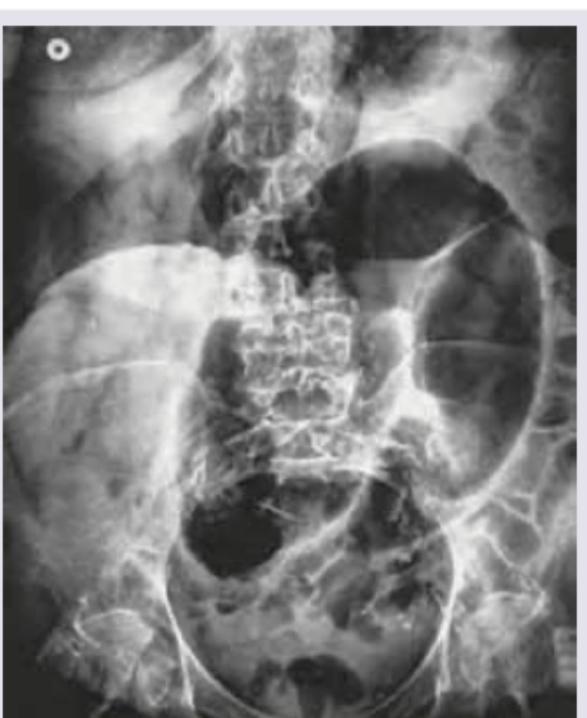

The diagnosis of this patient with left-sided abdominal pain and tyre-like feel of abdomen is?

Explanation: ***Sigmoid volvulus*** - The image shows massively dilated loops of bowel forming an **omega loop** or "inverted U" appearance, characteristic of **sigmoid volvulus**. The "tyre-like feel" upon palpation is consistent with a distended, gas-filled colon. - Clinical presentation with **left-sided abdominal pain** and signs of **large bowel obstruction** further supports this diagnosis, especially with the characteristic radiological findings. *Diverticulitis* - Diverticulitis typically presents with **left lower quadrant pain**, fever, and localized tenderness, but not usually with the massive abdominal distension and "tyre-like" feel seen in major bowel obstruction. - Radiological findings in diverticulitis often include **pericolic fat stranding**, wall thickening, and diverticula, rather than dramatically dilated bowel loops. *Paralytic ileus* - **Paralytic ileus** involves generalized bowel distension due to decreased peristalsis, often affecting both small and large bowel, rather than the localized, massive dilation of a single segment as seen here. - While there is distension, the distinct "inverted U" or omega loop configuration pointing to a specific segment of the bowel causing obstruction is not a feature of paralytic ileus. *Intussusception* - **Intussusception** is more common in children and typically presents with intermittent abdominal pain, vomiting, and "current jelly" stools, not primarily with palpable mass or a "tyre-like" feel on the *sigmoid* colon as described. - Radiologically, intussusception might show a "target sign" on ultrasound or an absence of gas distal to the obstruction, not the massively dilated sigmoid loop seen in the radiograph.